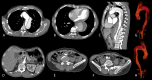

Introduction: The management of thoracic aortic disease involving the ascending aorta, aortic arch and descending thoracic aorta are technically challenging and is an area in constant development and innovation.

Results: A total of 95 patients treated for thoracic aortic diseases in this period, 18 underwent hybrid treatment and entered in this study. The average ages were 62.3 years. The male was present in 66.7%. The technical and therapeutic success was 94.5% e 83.3%. The perioperative mortality rate of 11.1%. There is any death during one-year follow- up. The reoperation rates were 16.6% due 2 cases of endoleak Ia and one case of endoleak II. There is any occlusion of anatomic or extra anatomic bypass during follow up.

Conclusion: In our study, the hybrid treatment of aortic arch disease proved to be a feasible alternative of conventional surgery. The therapeutic success rates and re- interventions obtained demonstrate the necessity of thorough clinical follow-up of these patients in a long time.